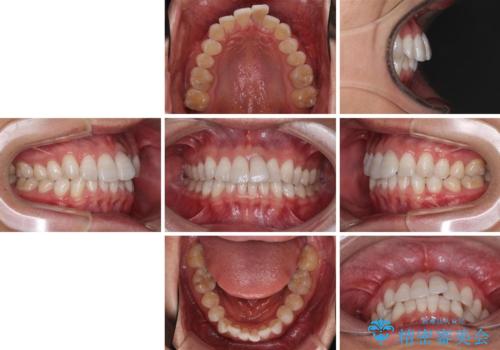

- 前歯のデコボコを治したいとのことで来院された患者様です。

上下顎ともに歯列全体の後方移動とIPR(歯と歯の間を削る)によってデコボコが解消するように設計し、インビザラインにより治療を行うこととしました。

矯正治療後、前歯の形と色が気になるとのことでしたが、大分前に失活している(神経が取り除かれている)歯であり、その影響で変色しているため、オールセラミッククラウンによる補綴治療をおすすめいたしました。